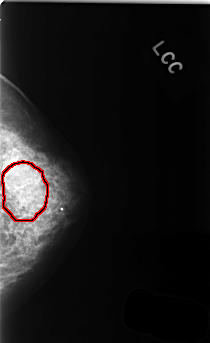

C_0368_1.LEFT_CC

FILE: C_0368_1.LEFT_CC.OVERLAY

TOTAL_ABNORMALITIES 1

ABNORMALITY 1

LESION_TYPE CALCIFICATION TYPE AMORPHOUS DISTRIBUTION SEGMENTAL

ASSESSMENT 4

SUBTLETY 2

PATHOLOGY BENIGN

TOTAL_OUTLINES 1

BOUNDARY